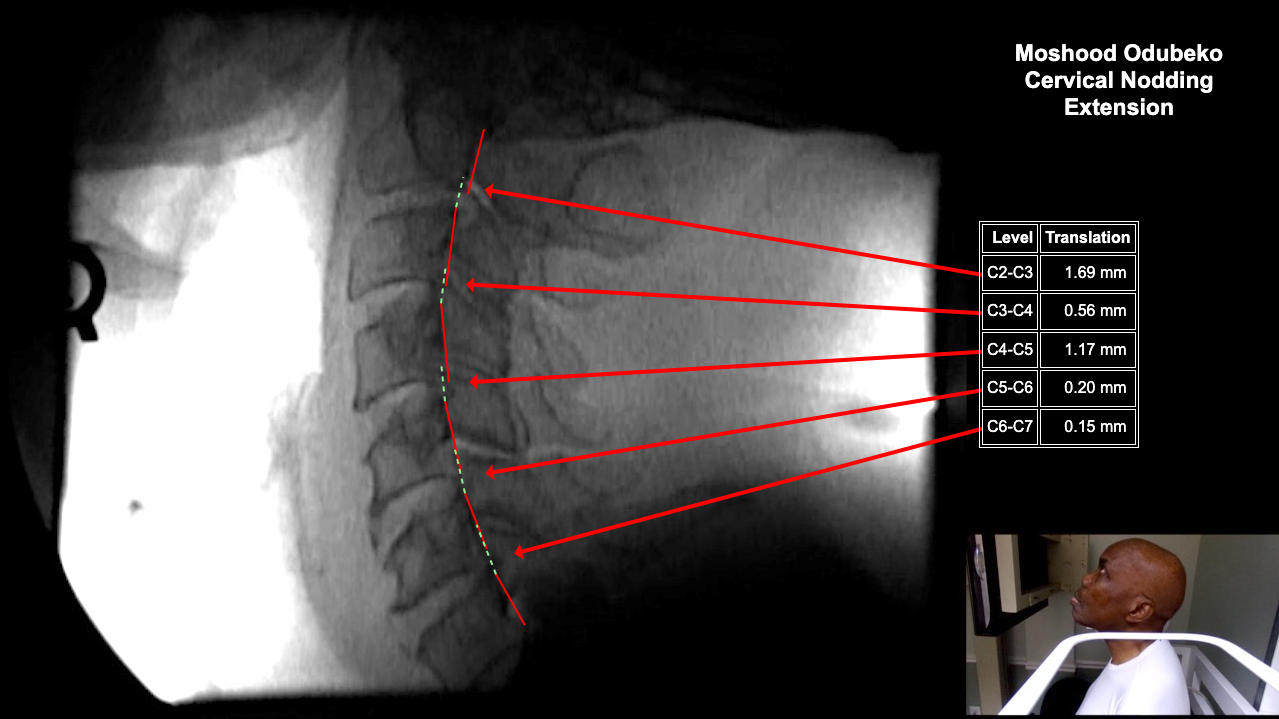

Image 2